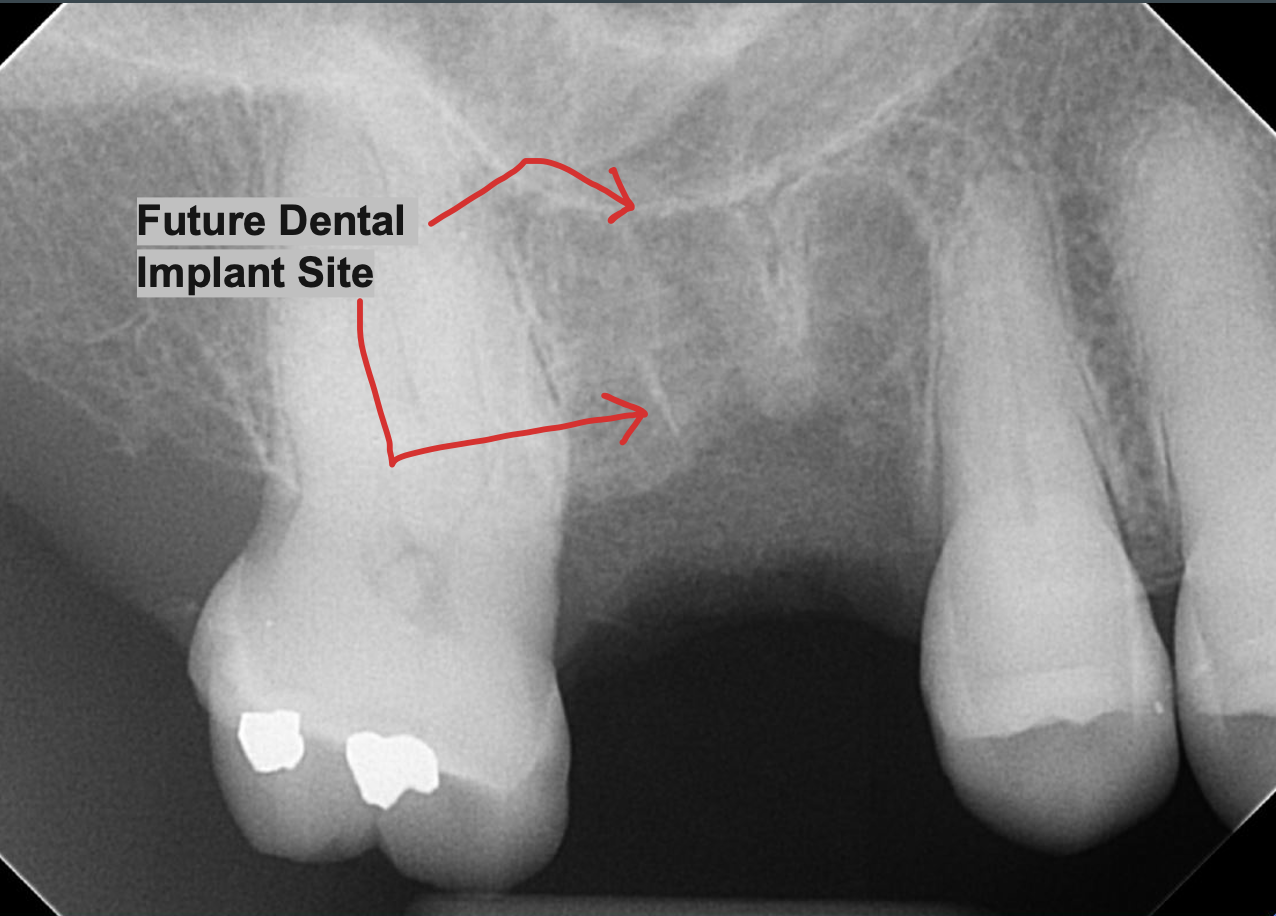

👀 Step 1: Pre-Op Evaluation

Before removing the tooth, we assessed bone health and root position with detailed imaging. In this case, the tooth had a prior root canal and a cavity on the back side, which caused the crown to loosen and eventually fall off. This tooth could not be saved by a new crown, so it needed to be extracted to prevent risk of infection and further damage of surrounding tissue. After reviewing alternative options, this patient is planning on a future dental implant to restore the site.

Images:

X Ray of tooth #18 Prior to Extraction

✅ Purpose: understand root formation, nerve anatomy, and ensure the socket walls are intact for grafting.